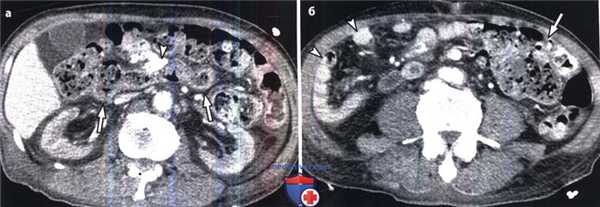

(г) В дистальной части сигмовидной кишки визуализируется переходная зона (стрелки) с ровными контурами. Образование, приводящее к обструкции, не выявляется. Отмечается гидронефроз правой почки (указатель), обусловленный сдавлением увеличенной сигмовидной кишкой правого мочеточника в области его дистальной части.

У новорожденных правильный диагноз можно установить с помощью бариевой клизмы (Vorobyovet al.,2010). Взрослым пациентам, страдающим болезнью Гиршпрунга, для исключения других органических причин непроходимости, таких как рак толстой кишки, проводят КТ. При этом выявляется расширенная толстая кишка, заполненная фекалиями, с узкой переходной зоной и суженным дистальным сегментом в отсутствии видимой причины обструкции.

1. Болезнь Гиршпрунга развивается вследствие нарушения краниокаудальной миграции нейронов во внутриутробном периоде. Иногда правильный диагноз не удается установить до второго или третьего десятилетия жизни, так как симптомы успешно купируются клизмами и слабительными.

При КТ выявляется расширение толстой кишки, заполненной фекалиями, с узкой переходной зоной в отсутствии видимой причины обструкции. Дистальные отделы, как правило, спавшиеся.